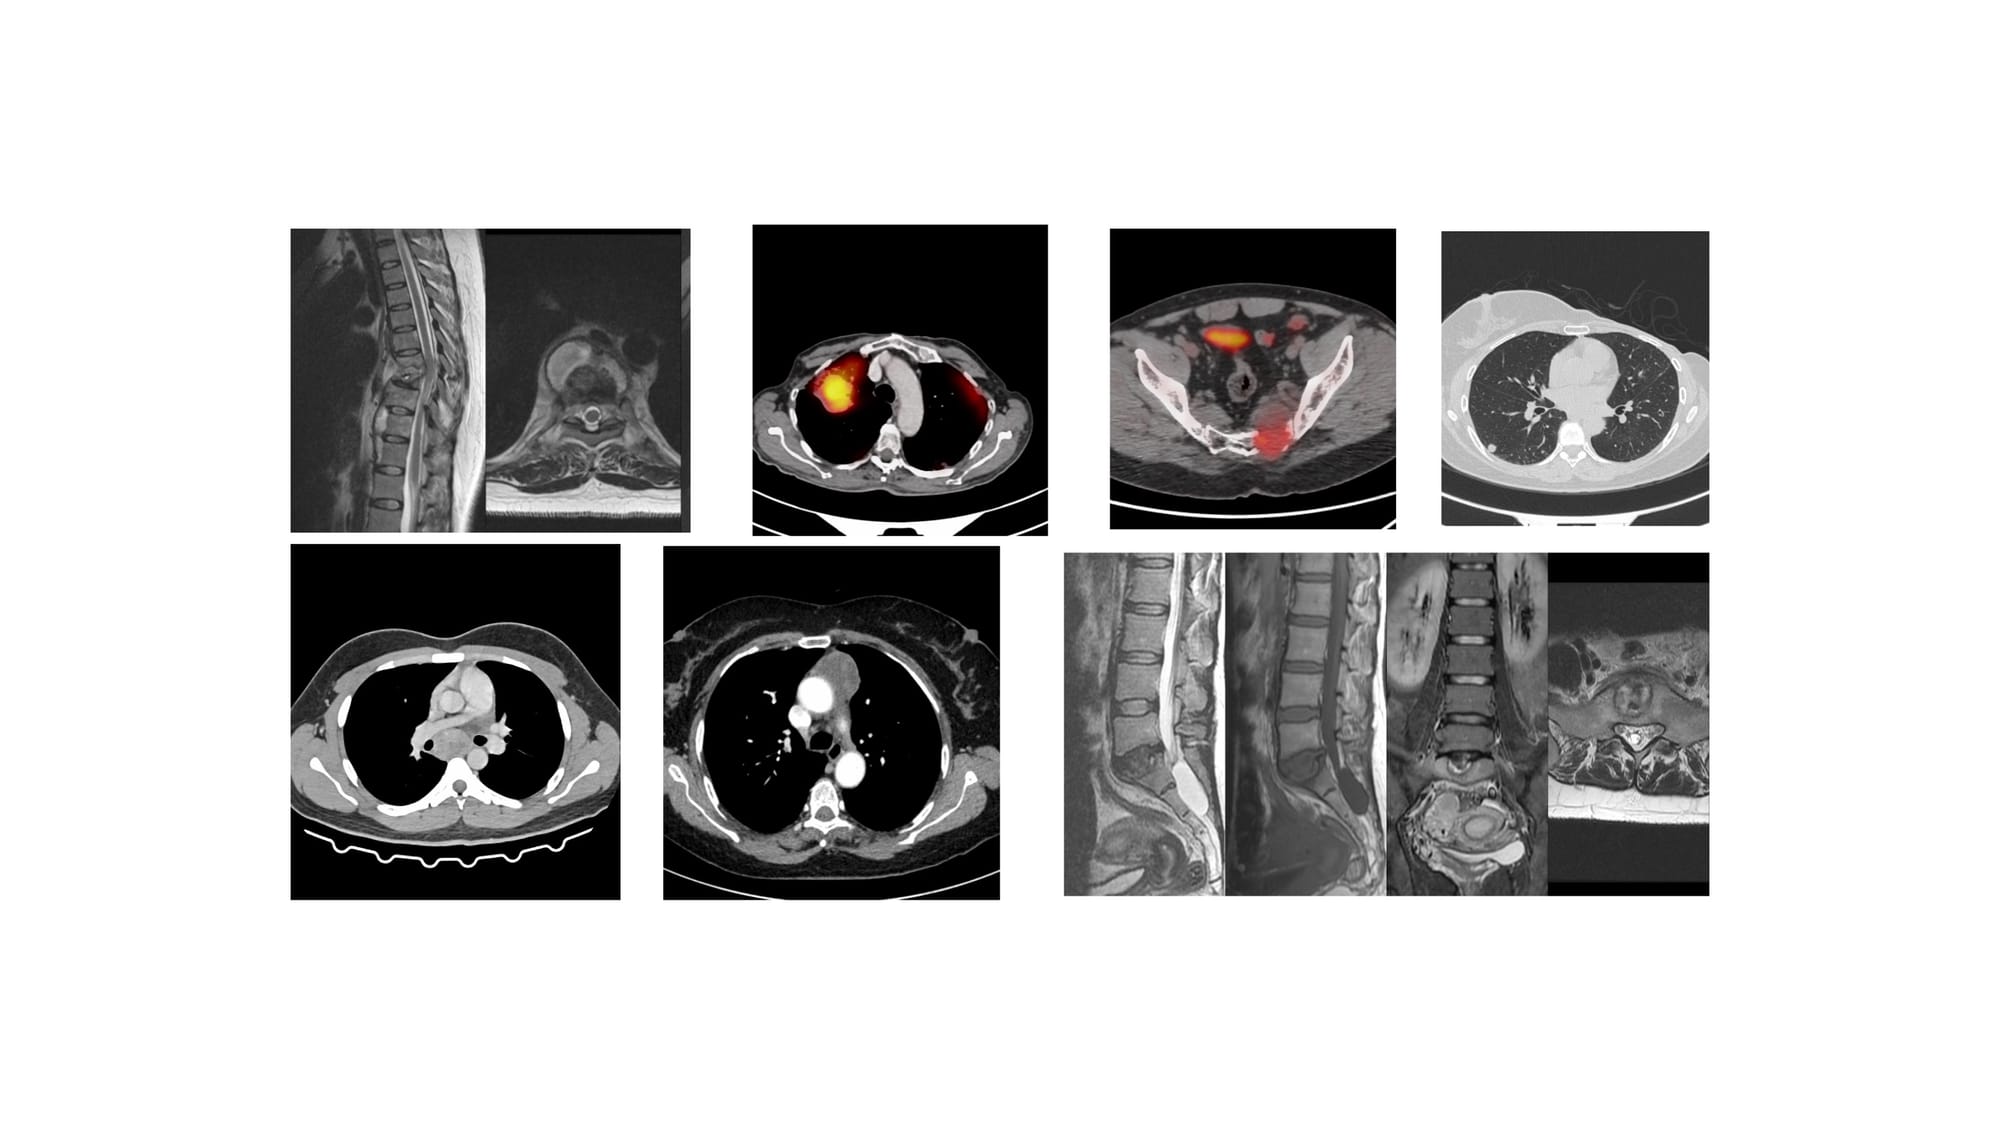

The 7 Cases for YouTube Live on 08 Jan at 7 PM Indian Standard Time

Bhavin Jankharia - 04 January 2026